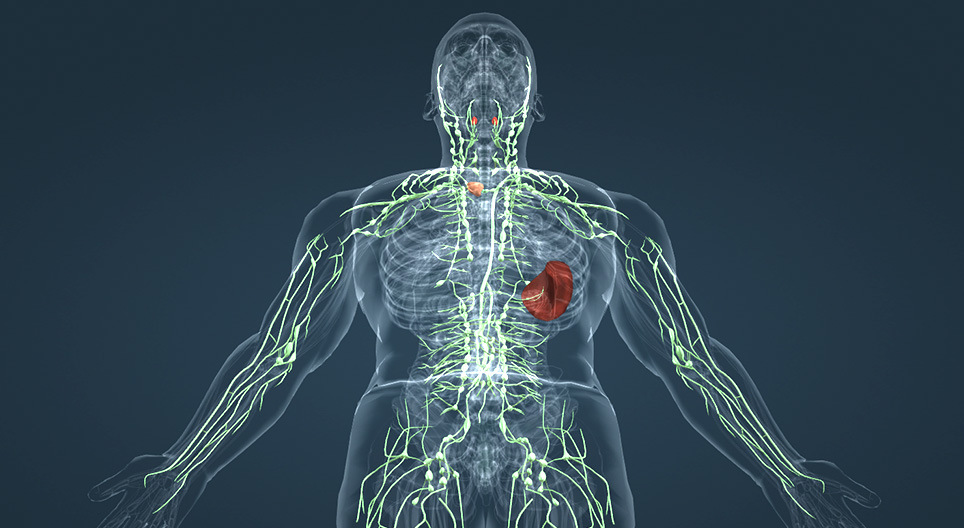

Де знаходиться лімфа у людини?

По-перше, лімфа циркулює в лімфатичних судинах. Вони схожі на кровоносні, тільки тонші. Ці судини проходять практично по всьому тілу – у руках, ногах, шиї, грудях, животі. Саме по них лімфа повільно рухається від тканин до лімфатичних вузлів, а згодом повертається в кровообіг.

По-друге, лімфа накопичується й фільтрується в лімфатичних вузлах. Це ті самі “горошини”, які можна намацати на шиї, під пахвами або в паху. Вузли є:

- на шиї;

- під нижньою щелепою;

- у пахвових западинах;

- у паховій зоні;

- всередині грудної клітки та черевної порожнини.

Там лімфа очищується від бактерій, вірусів і токсинів.

По-третє, лімфа знаходиться в міжклітинному просторі. Спочатку це тканинна рідина, яка омиває клітини. Частина її повертається в кров, а частина потрапляє в лімфатичні капіляри й стає лімфою. Тобто лімфа буквально починається між клітинами.